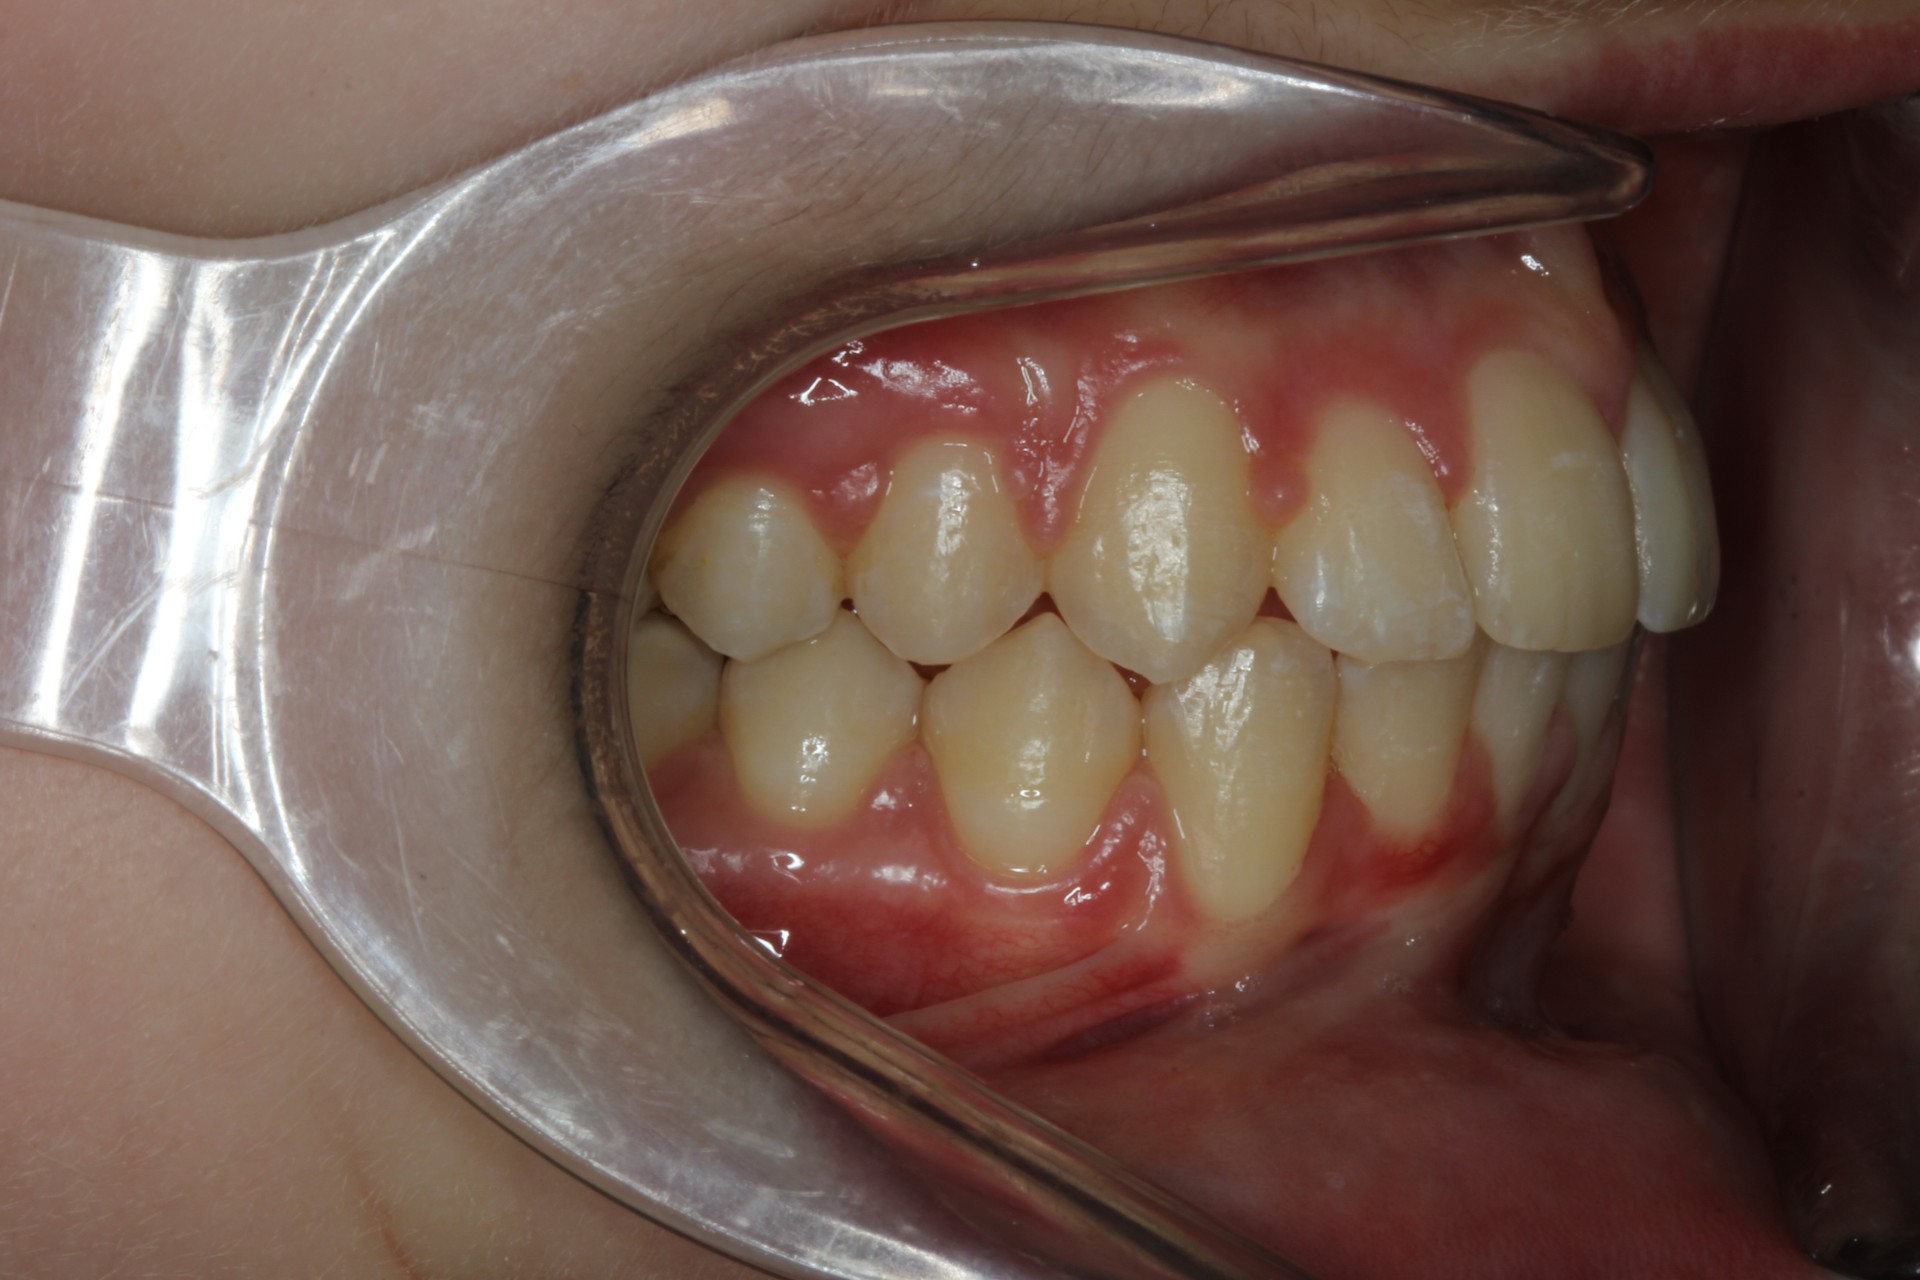

Protruding front teeth – Child case